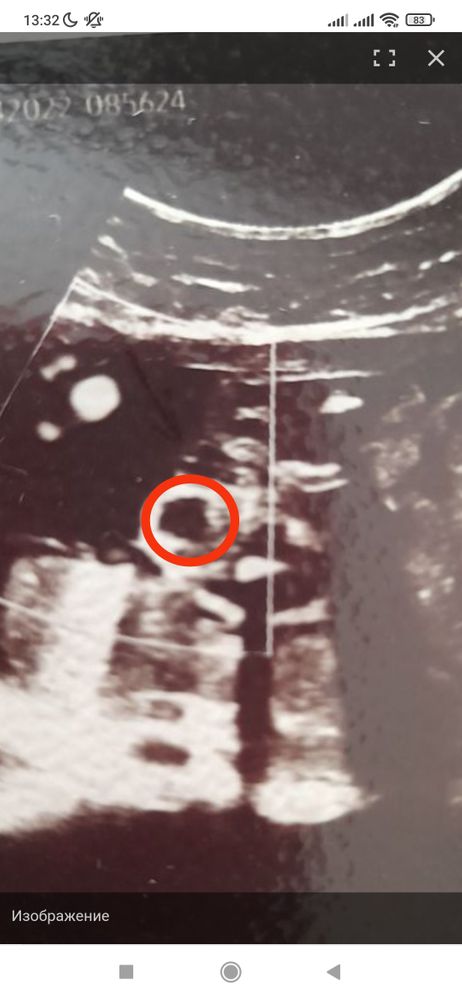

Не понятно ничего))). А что это за кружок чёрный по центру ребёнка? (Мне как-то узистка дала фотку ребёнка, я её весь день вертела, так и не поняла, что она сфотографировала 😄)

Изображение Екатерина, я вот про это. Это пятка? Просто хоть понимать, от чего отталкиваться))

Twilight sparkle, Изображение нет,это принадлежность к полу))